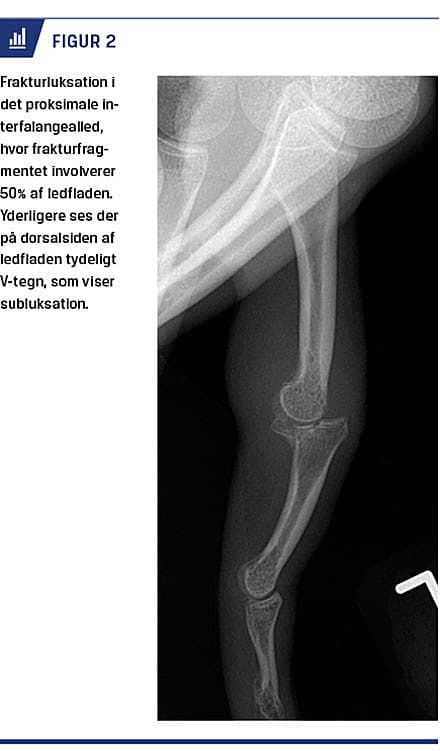

Frakturluksationer er hyppigst dorsale [22] og ses bedst i lateral projektion. Subluksationer ses som et

V-formet hul i den dorsale ledlinje (V-tegn) [23]. Der forekommer ofte læsion eller avulsionsfraktur af volarpladen med tab af volar støtte [2]. Mindre skader behandles med buddy taping og tidlig intensiv træning for at forhindre senfølger. Ved større avulsionsfragmenter kan de kollaterale ligamenter miste kontakten til mellemphalanx, som derfor sublukserer dorsalt (Figur 2) [24]. Volare frakturluksationer kan være ledsaget af

læsion af ekstensorsenens centralsnip, og der kan ses hyperfleksion med manglende ekstension i PIP-leddet (Elsons test) [2], hvilket kan være svært at teste akut. Frakturluksationer betragtes som stabile, når mindre end 30% af ledfladen er involveret, og når en eventuel subluksation forbliver reponeret i mindre end 30 graders fleksion [23]. Derudover skal leddet kunne ekstenderes og flekteres i en glidende bevægelse [3]. Frakturluksationer behandles med extension block-skinne i fuld fleksion, men med begrænset ekstension i PIP-leddet [22]. Over tre uger øges ekstensionen gradvist [23]. Volare frakturluksationer behandles med skinne i fuld ekstension og begrænset fleksion [2]. Ved involvering af mere end halvdelen af ledfladen er frakturluksationer ustabile [3]. Der kan foretages extension block pinning, hvor der sættes en K-tråd intraartikulært i den proksimale phalanx for at blokere ekstensionen i PIP-leddet og dermed forhindre subluksation eller luksation [23]. Ved kominutte frakturer af basis af mellemphalanx kan man anvende ekstern fiksering [22], eventuelt kombineret med intern fiksering og tidlig aktiv bevægelse [23]. Teknikken kan være udfordrende, og der er risiko for infektion og frakturskred [23].